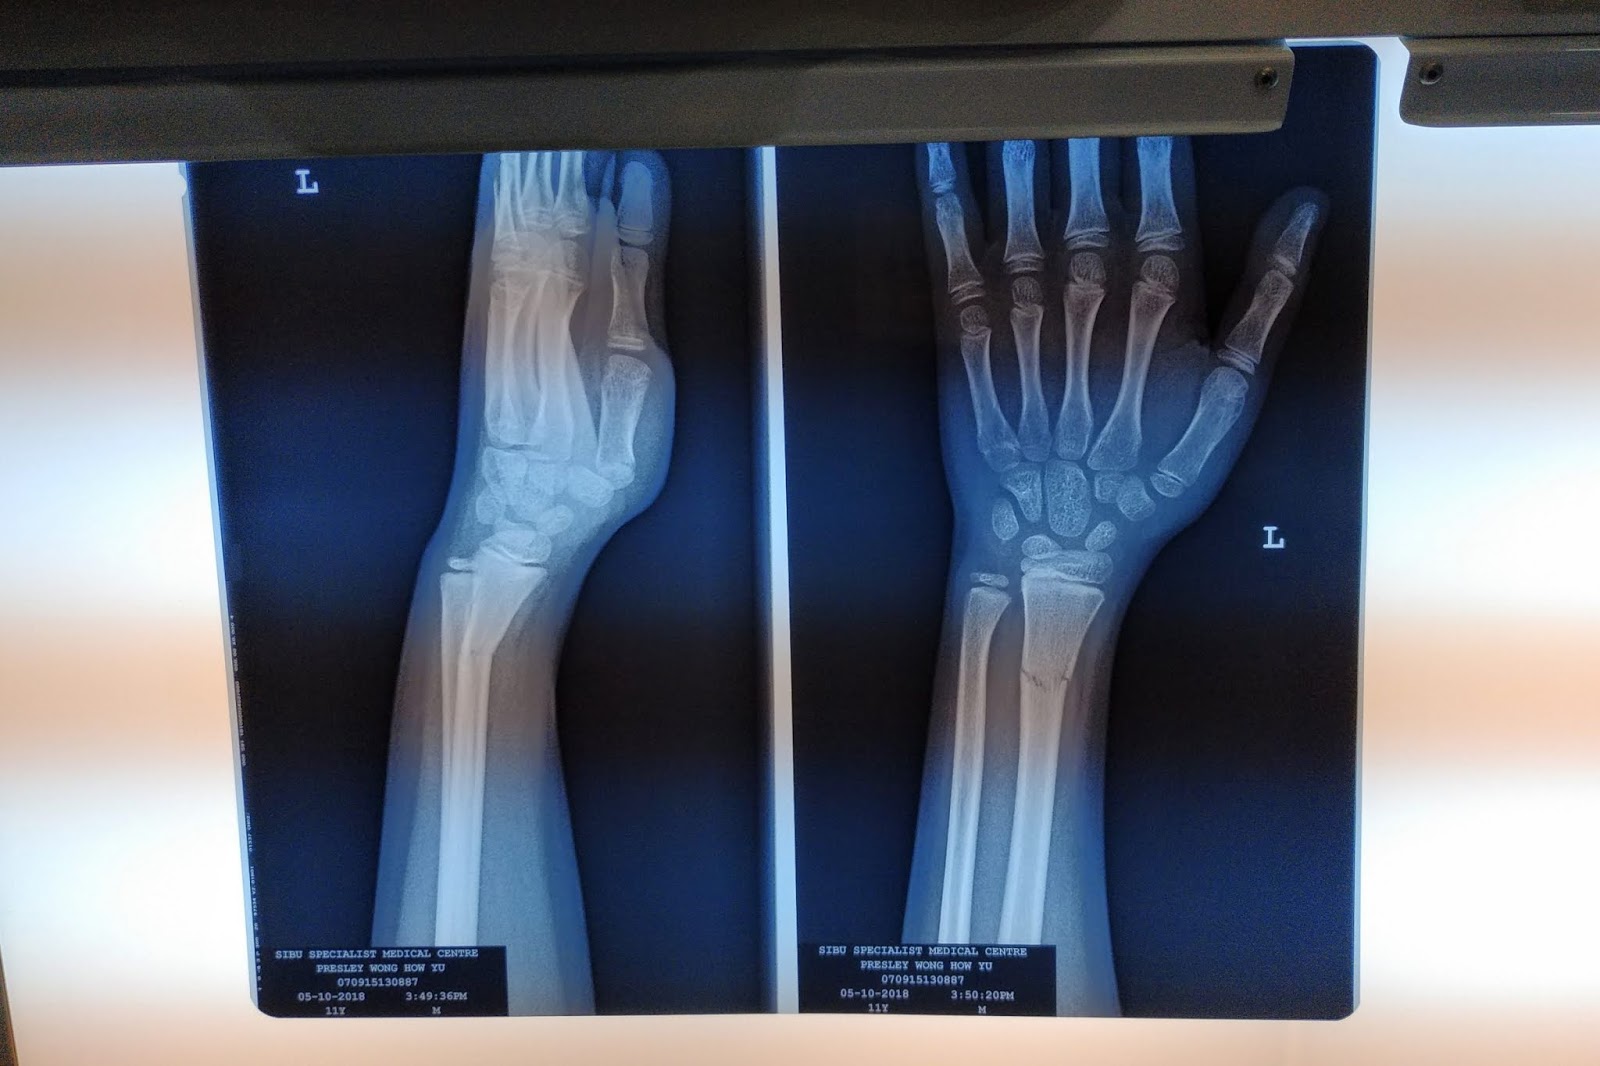

小男孩通常都是比较顽皮,不过我家的是有点过度顽皮,又喜欢逞强,小时候就常常顽皮弄伤自己,而这次是跌到把手商了。经过检查骨折了,还好不是太严重,但是需要麻醉把它调整回原来的位置,打上石膏,让它慢慢康复。小P第一次进手术房,吓到哭了,一脸无奈的表情,希望经过这次以后会比较长进点。

受伤有点弯曲手

骨折了